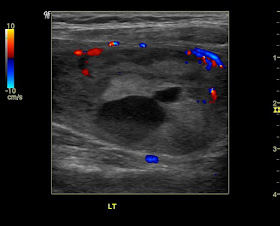

Colloid nodule of the thyroid- 3D and elastography study:

These ultrasound images were taken with the GE P6 pro.

Observe the large colloid nodule in the left lobe with a cyst within it.